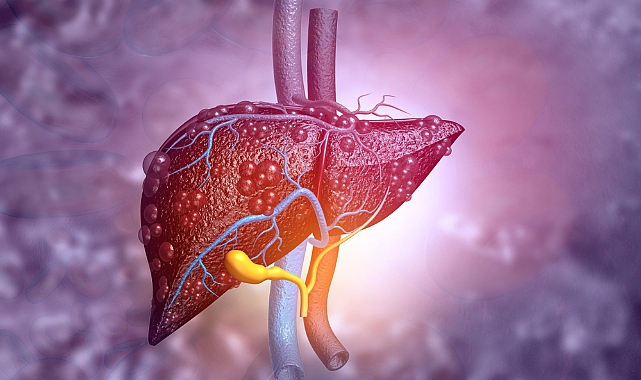

Medicana International Ankara Hastanesi Gastroenteroloji Uzmanı Doç. Dr. Muhammed Fatih Karakaya, tip 2 diyabet, yüksek kolesterol, alkol tüketimi ve karaciğer yağlanmasının siroz ile kanserin başlıca nedenleri arasında yer aldığını söyledi.

Karaciğer yağlanmasının çoğu zaman belirti vermediğini söyleyen Medicana International Ankara Hastanesi Gastroenteroloji Uzmanı Doç. Dr. Muhammed Fatih Karakaya, bu durumun karaciğer kanseri ve metabolik sendromla ilişkili olarak kalp damar hastalıkları ve diğer kanserlerin riskini de artırdığını vurguladı.

Karaciğer yağlanmasının, karaciğerde olması gerekenden daha fazla miktarda yağ birikimi olarak tanımlandığını kaydeden Doç. Dr. Muhammed Fatih Karakaya, "Her karaciğer yağlanması hastası aynı risk grubunda bulunmaz. Basit yağlanma dediğimiz grupta karaciğer büyümesi varken, ilerleyen süreçte biriken yağın karaciğer hücrelerinde oluşturduğu inflamasyon (steatohepatit) ve hasara bağlı siroz da gelişebilmektedir" ifadesini kullandı.

Karaciğer yağlanmasının yıllar içinde karaciğer sirozuna sebep olabilecek hepatit tablosu geliştirebileceğini belirten Karakaya, viral hepatitlerin etkin tedavisiyle birlikte, karaciğer yağlanmasının sirozun en sık görülen nedeni haline geldiğini ifade etti. Karakaya, ayrıca, karaciğer kanseri ve metabolik sendromla ilişkili olarak kalp damar hastalıkları ve diğer kanserlerin riskinin de artırdığını vurguladı.